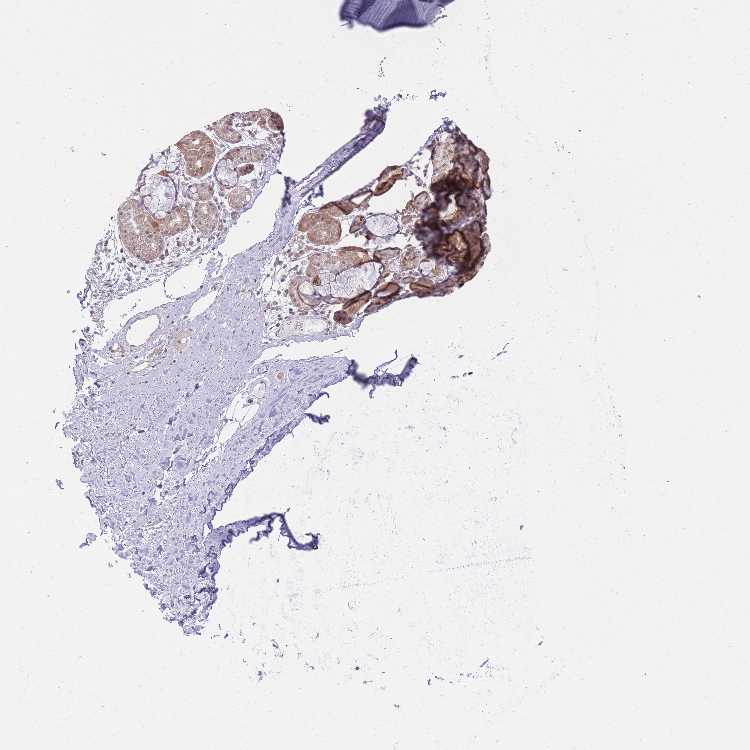

SOFT TISSUE 1 - Antibody stainingi

Antibody staining in the annotated cell types in the current human tissue is reported as not detected, low, medium, or high, based on conventional immunohistochemistry profiling in selected tissues. This score is based on the combination of the staining intensity and fraction of stained cells.

Each image is clickable and will lead to virtual microscopy that enables deeper exploration of all samples and also displays staining intensity scores, fraction scores and subcellular localization as well as patient and tissue information for each sample.

Antibody HPA041009Antibody HPA043501Antibody HPA048971Antibody HPA049178Antibody HPA050086

Chondrocytes --Not detected--

Fibroblasts Not detectedNot detectedNot detectedNot detectedNot detected

Peripheral nerve Not detectedNot detected--Not detected